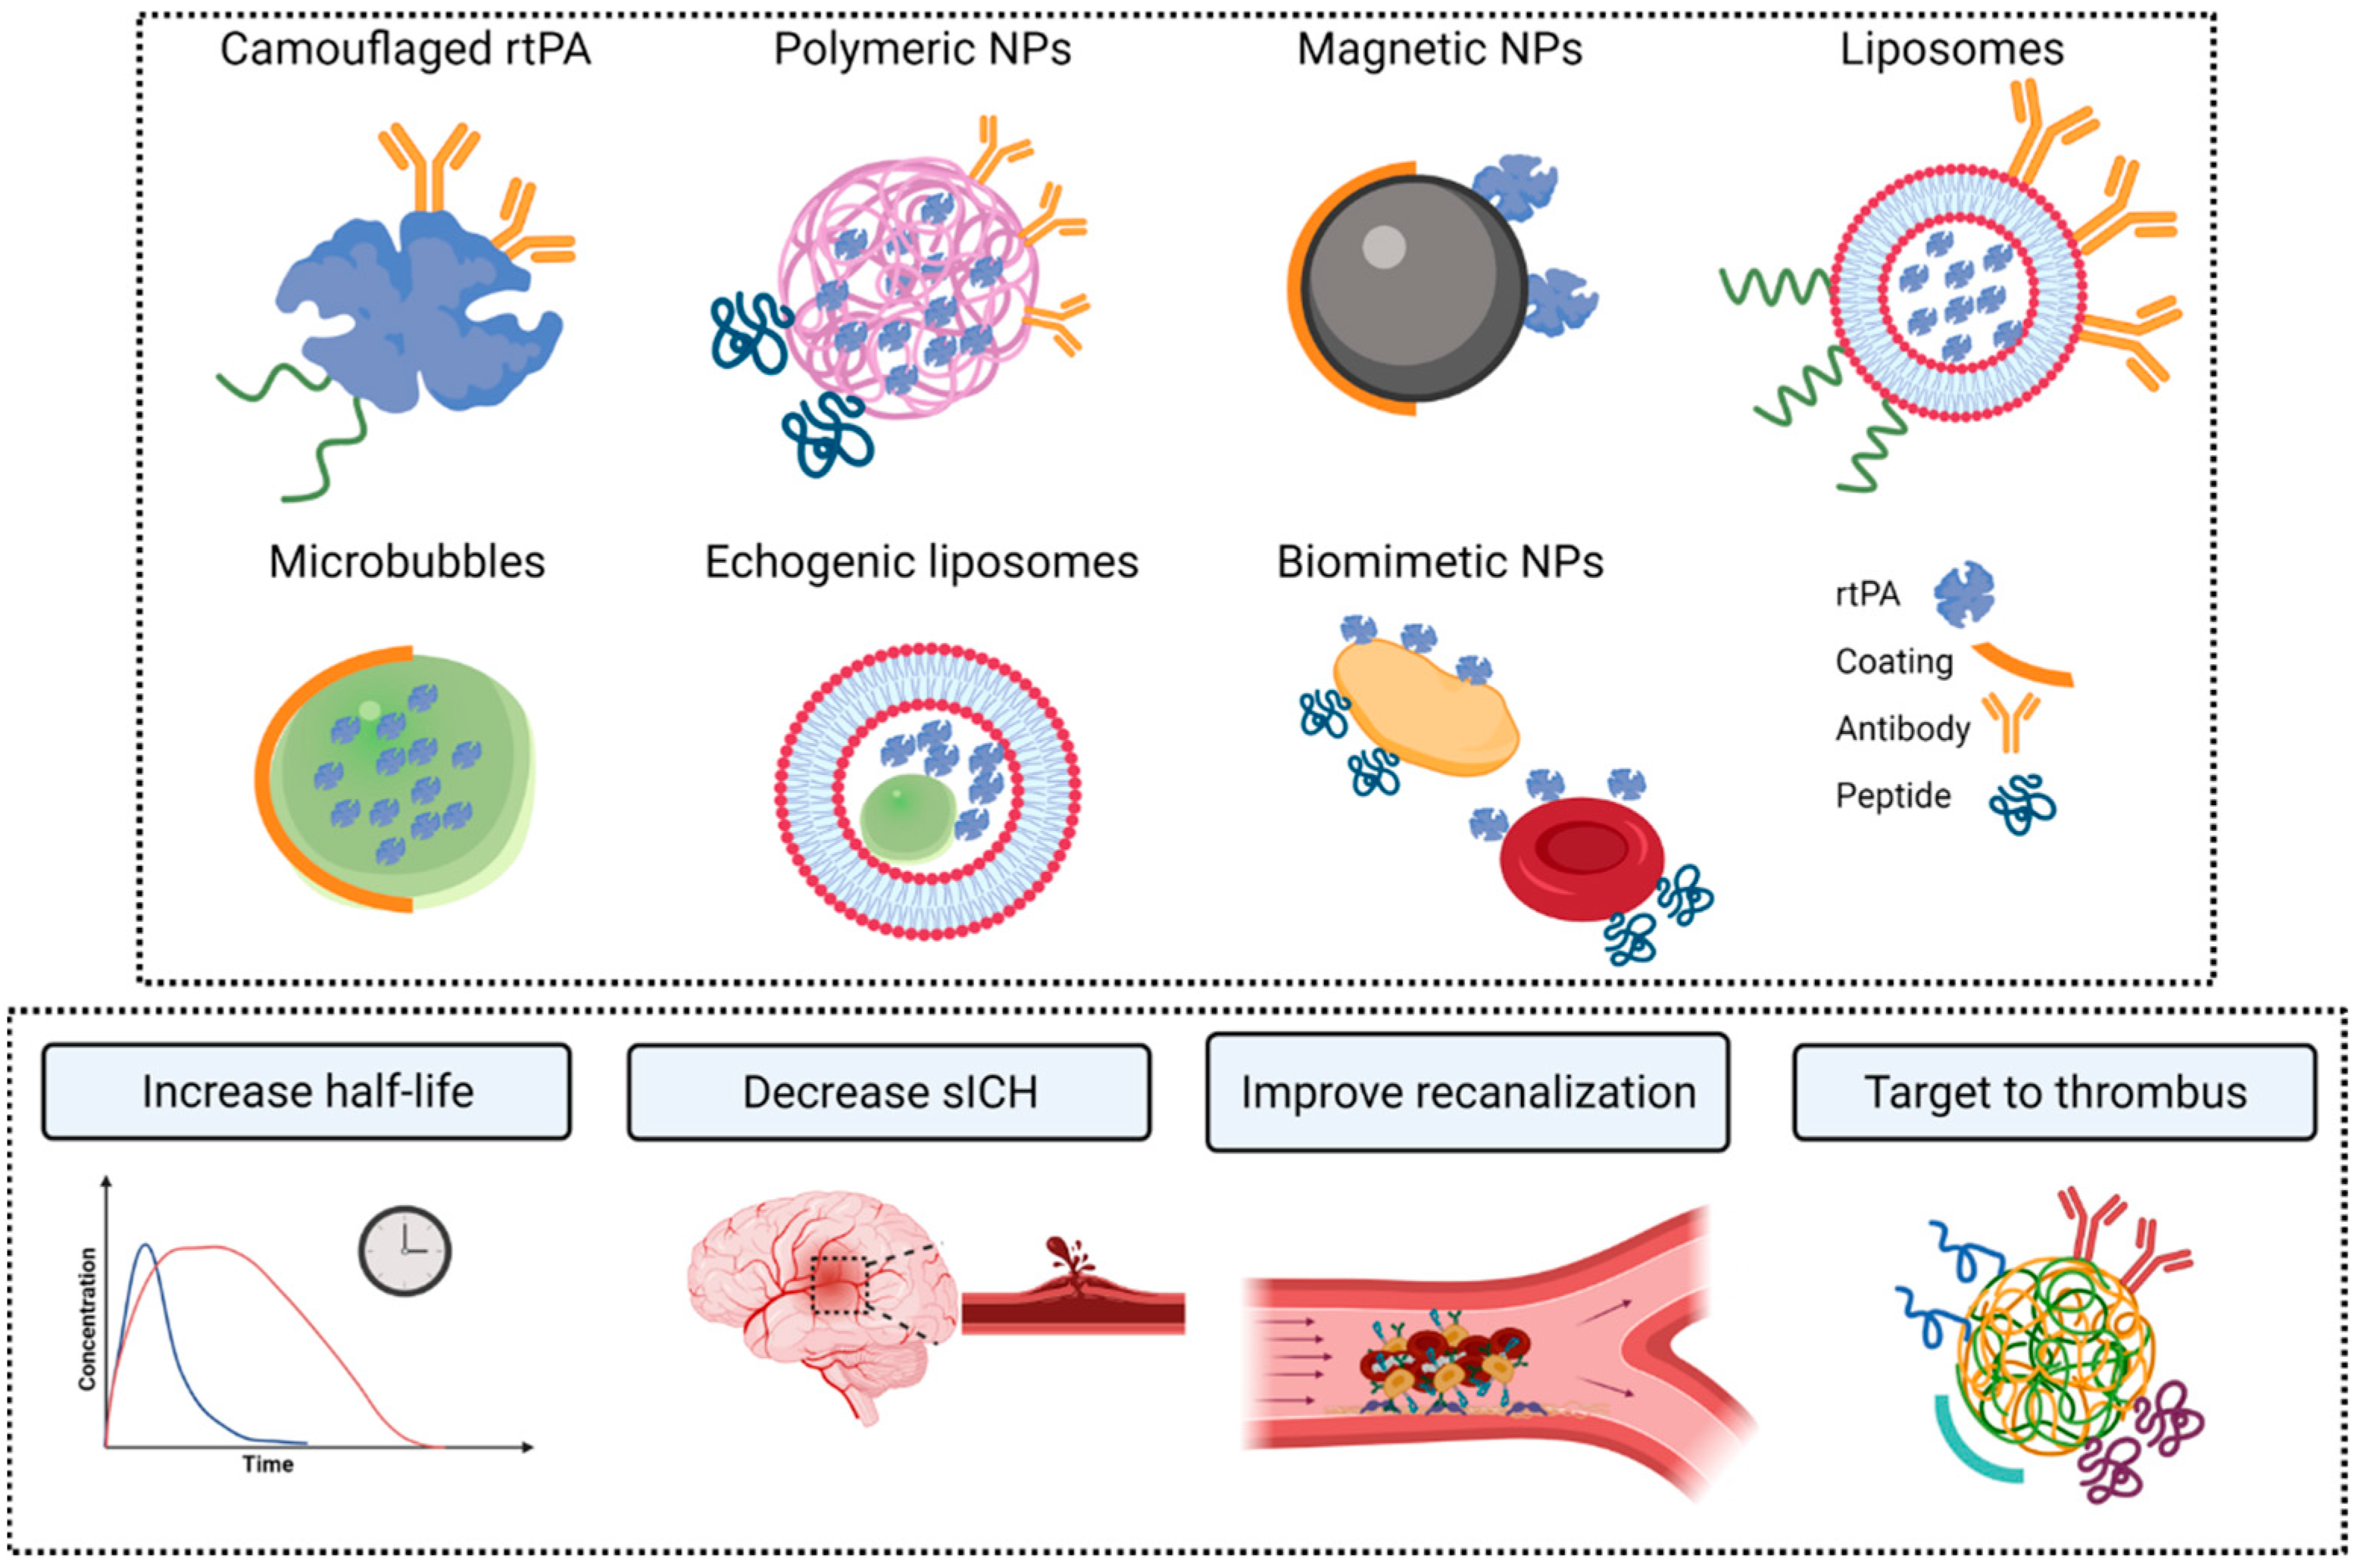

3.1. Nanocarriers for rtPA

3.2. Clot Targets for rtPA Nanocarrier Vectorization

3.3. Triggering Controlled Release